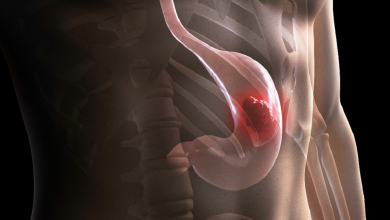

سرطان المعدة

علامات قد تشير إلى سرطان المعدة

يعتبر التشخيص المبكر لسرطان المعدة مشكلة كبيرة، حيث عادة ما يتجاهل الشخص “أجراس الإنذار الأولى”، لأنها ليست محددة. فما هي…